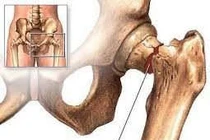

Trật khớp háng bẩm sinh là một bệnh lý nguy hiểm song lại khó phát hiện sớm khi trẻ mới chào đời. Nếu được phát hiện sớm trước 6 tháng tuổi điều trị đơn giản, nhưng đa phần trẻ biết đi mới được phát hiện nên gây nhiều di chứng.

(khoahocdoisong.vn) - Hoại tử vô khuẩn chỏm xương đùi là tình trạng chỏm xương đùi bị phá hủy mà nguyên nhân là do thiếu nuôi dưỡng. Nguyên nhân gây bệnh có thể do chấn thương của khớp háng (gãy cổ xương đùi, trật khớp háng...), uống nhiều rượu, hút nhiều thuốc lá, lạm dụng corticoid, bệnh lý mạn tính toàn thân...